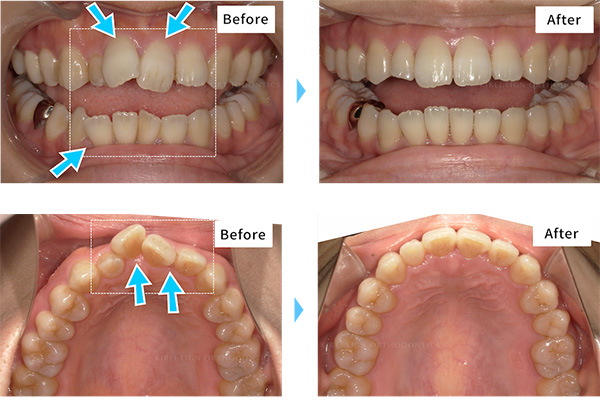

【5~7回の症例】

標準的な回数で治療が終了した症例です

-

- 治療期間

- 約8ヶ月(キレイラインを7回実施)

- 治療費用

- 290,000円(税込319,000円)

-

No

40028084

-

症状

ガタガタな歯

-

再診料

(6回) 18,000円 (税込19,800円)

-

追加治療

なし

- ※効果には個人差があります。